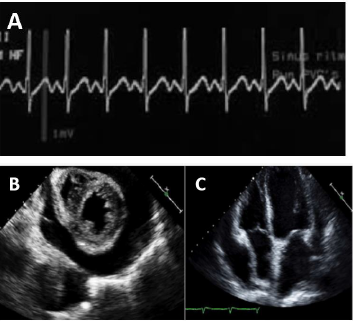

O registro do ECG no monitor (A) e o ecocardiograma de urgência na beira do leito (B e C) estão dispostos a seguir.